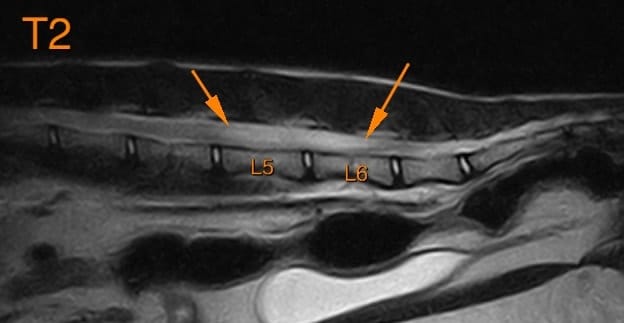

Un examen d’imagerie en coupe (tomodensitométrie ou IRM) est nécessaire afin d’établir un diagnostic présomptif de gliome. L’IRM montre une grande supériorité par rapport à la tomodensitométrie (= scanner) lors de suspicion de gliome cérébral et médullaire. Ces examens montrent généralement des lésions intraparenchymateuses uniques (des cas de gliomes multiples ont également été décrits), bien ou mal définies, avec des degrés de rehaussement variés et souvent un effet de masse sur les tissus sains.

Lors d’atteinte de la moelle épinière, un examen myelo-tomodensitométrique (= myéloscanner) est souvent plus précis qu’un scanner simple car il permet de mieux voir une lésion intramédullaire mais nécessite souvent une confirmation par IRM afin de les différentier des autres lésions intramédullaires (embolie fibrocartilagineuse, myélite …)